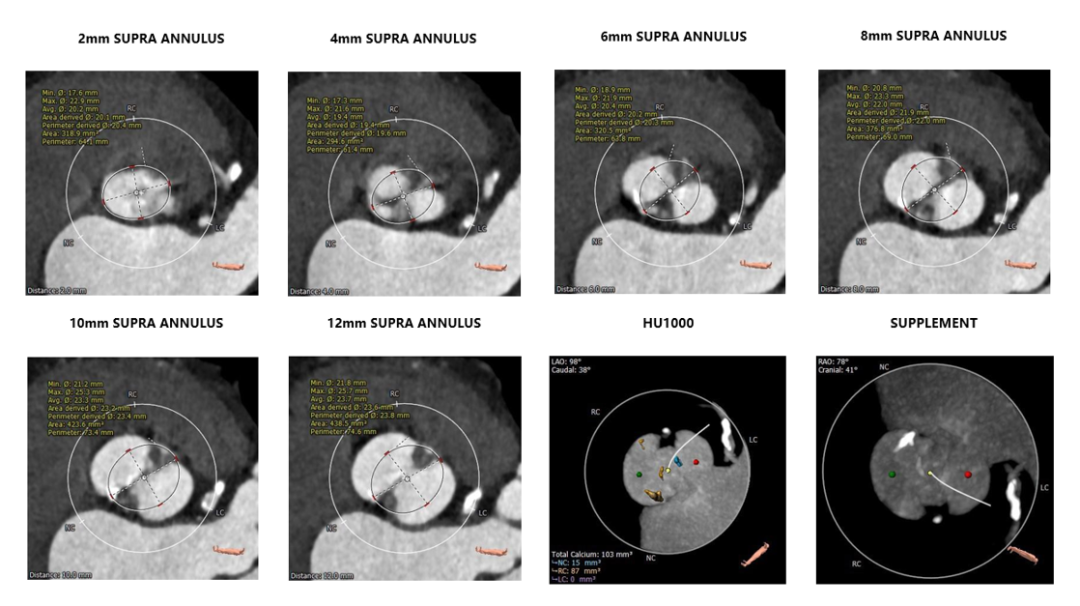

1.主动脉瓣瓣环周长64.3,平均周长径20.1。

2. Type0型二叶式主动脉瓣,轻度钙化,左右冠脉不共窦,右冠窦瓣叶附着缘后联合区有钙化分布呈连续条状,瓣叶增厚增长。

3. 左右冠脉开口高度可,左冠多发钙化。

4. 瓦氏窦、窦管交界、升主动脉内径可。

5. 非横位心,流出道呈收口状,收缩期小左室,心肌增厚;主动脉弓宽度及弓部夹角可。

主动脉根部评估

瓣环上解剖结构评估